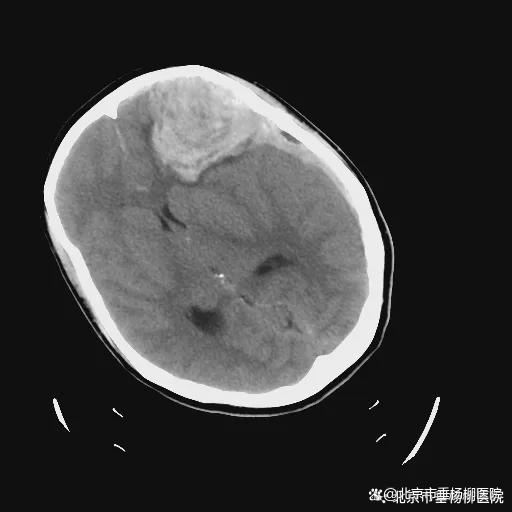

在接诊后,急诊科医师迅速启动绿色通道,头部CT检查显示脑出血,且出血量较大,中线明显移位,随即联系医院神经外科会诊。

▲左侧额叶及硬膜下血肿(术前)